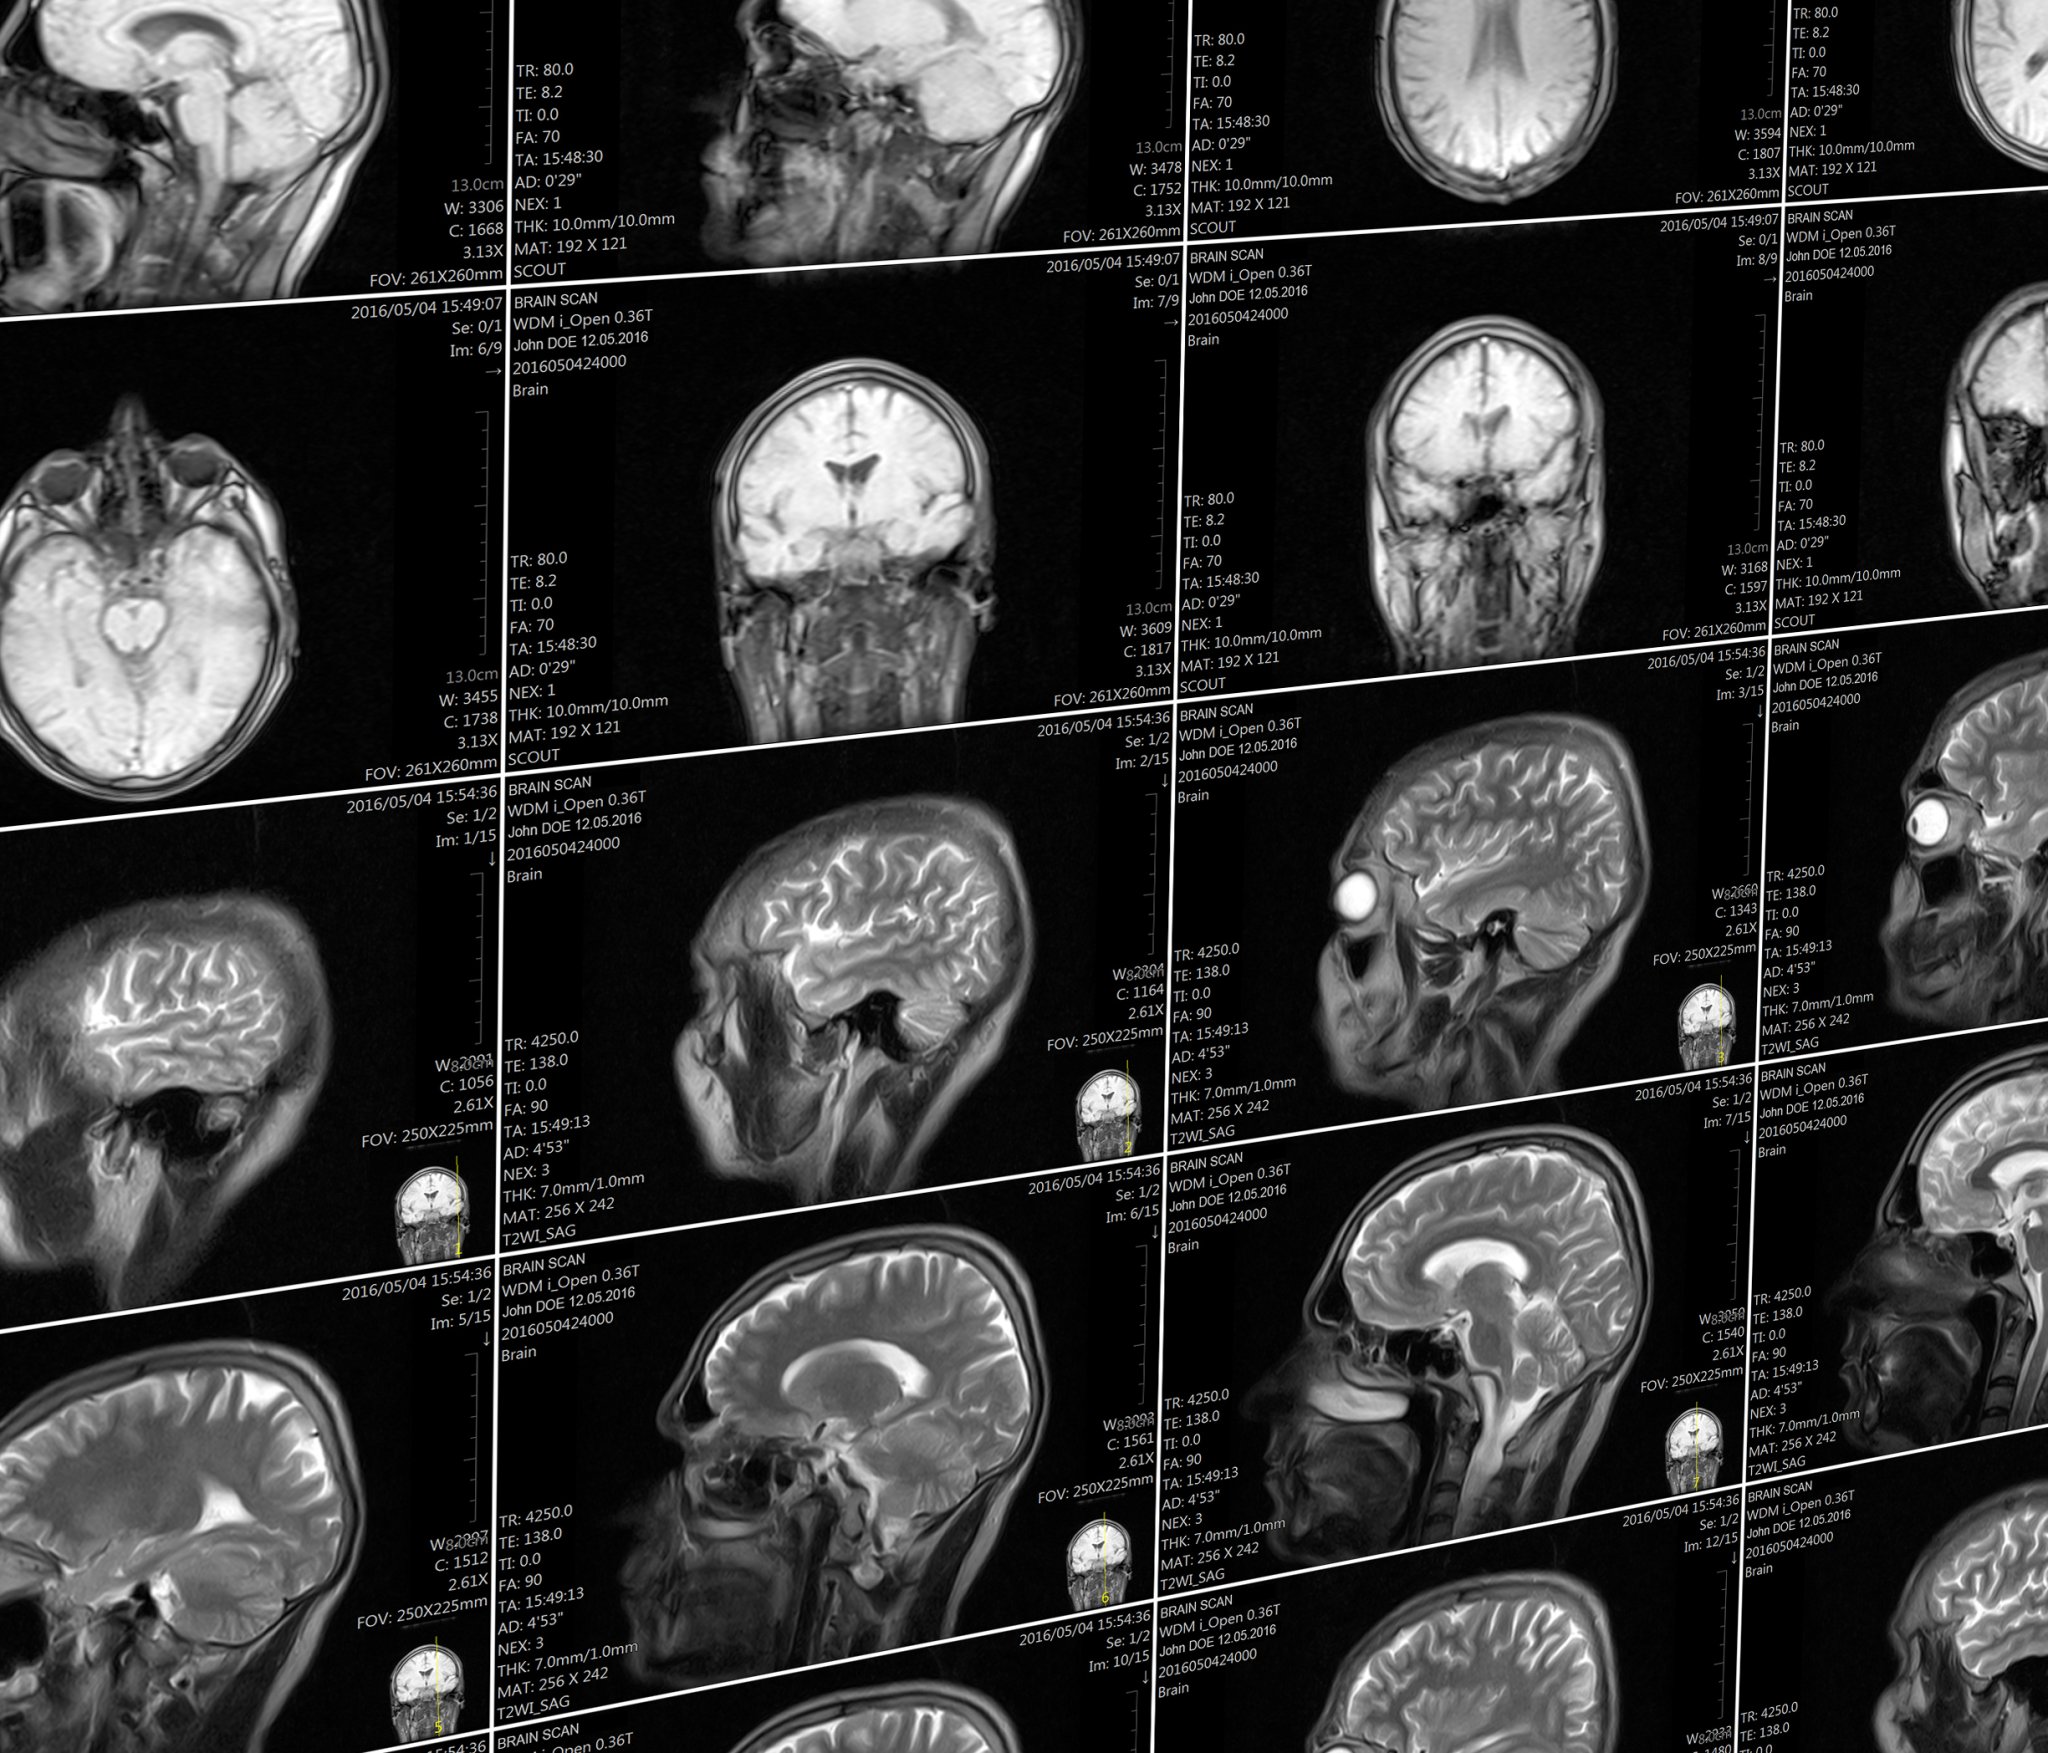

People with “Havana syndrome” have differences in their brains compared to healthy people.

Beginning in late 2016, government officials from the United States and Canada stationed in Cuba started reporting clusters of symptoms that seemed a bit like a concussion: a sudden onset of headaches, dizziness, and confusion after hearing a high pitched noise. The illness soon became referred to as “Havana syndrome” and the cause has been subject to intense debate, and some experts have suggested that the condition is purely psychological. But a new study, which found that those affected have differences in their brains compared to healthy people, pushes back on that skepticism.

The research builds on a previous study from the same research team outlining the neurological problems experienced by people who lived in Cuba and who reported symptoms. “This is the imaging findings that underlie those clinical symptoms,” says study author Ragini Verma, a professor of radiology and a brain imaging specialist at the University of Pennsylvania School of Medicine.

The new study, published in the Journal of the American Medical Association (JAMA), used brain scans to look at three different aspects of brain function in 40 people who were clinically evaluated after reported exposure to the as-yet undetermined phenomenon. It looked at the overall volume of various regions in their brains; at the fine structure of brain tissue in the cerebellum, which regulates movement and controls balance; and at the connectivity of brain networks involved in hearing, vision, and high-level cognitive skills like memory.

The analysis found that the patients who had been stationed in Cuba had less volume of white matter, which contains the parts of neurons that connect brain regions together, than the control groups. They had differences in their cerebellum to the control groups, and had lower connectivity in the auditory and visual networks of the brain (though not those involved in executive function).

Notably, Verma says, the patterns of changes in brain volume and in the cerebellum, were unlike the patterns of changes seen in any other diseases—they didn’t look like the changes seen in patients with traumatic brain injuries, for example, or other neurological conditions.

“To the best of my knowledge, this is something unique to these patients,” she says. Seeing a new pattern, she says, is extremely rare.

The findings do indicate, though, that there are structural and functional changes in the brain that offer a potential basis for clinical symptoms. It’s a counter to some criticisms levied on the team’s prior paper that evaluated the neurological symptoms of this patient group, which included skepticism that their experiences weren’t just psychogenic. “The clinical element said there should be a problem in the cerebellum, and the imaging showed changes in the cerebellum. It’s an objective measure,” Verma says.